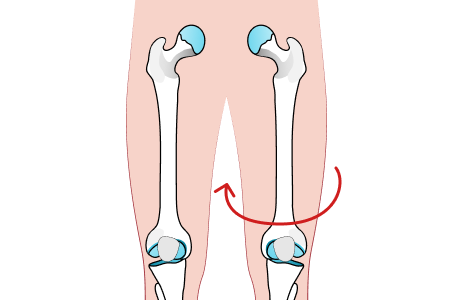

안짱다리 유형

대퇴골 내회전

허벅지 뼈가 안쪽으로 틀어진 경우

경골 내회전

종아리 뼈가 안쪽으로 틀어진 경우

중족골 내전

발이 안쪽으로 휘어 있는 경우